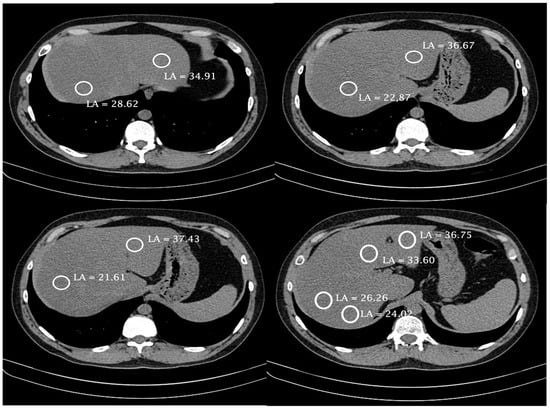

Liver steatosis was detected on chest or abdomen CT imaging and quantified by use of the liver attenuation coefficient measured in four sites of the liver parenchyma (two measures in the right lobe, one in the right-to-left lobe transition, and one in the left lobe) during the non-enhanced phase, as shown in Figure 1. The contrast is a confounding effect because it alters hepatic density, and there are no cut-off density value parameters that allow for characterizing steatosis in a post-contrast study. The most homogeneous areas of the liver parenchyma were chosen, avoiding vessels, the biliary tract, and focal liver lesions [27]. Later, the arithmetic mean of the four measures was calculated. Mean attenuation coefficient values ≤ 40 Hounsfield units were considered indicators of SLD [24,28].

Figure 1.

Computed tomography images and measurement sites of the attenuation coefficient in one of the patients evaluated in the study. LA, liver attenuation.